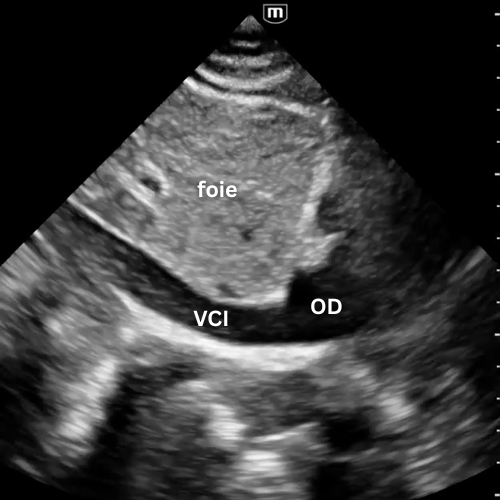

🔹 Vue Sous-costale (subxiphoïdienne)

→ Le cœur bouge-t-il ? y a-t-il du liquide ?

Placer la sonde sous l’appendice xiphoïde, dirigée vers l’épaule gauche, en s’aidant du foie comme amplificateur acoustique.

C’est la fenêtre universelle de la réanimation, utilisable pendant la RCP.

Elle permet de visualiser les quatre cavités, de détecter un épanchement péricardique même discret, et d’apprécier grossièrement la fonction myocardique.

Un simple regard suffit à trancher entre activité cardiaque présente ou asystolie réelle.